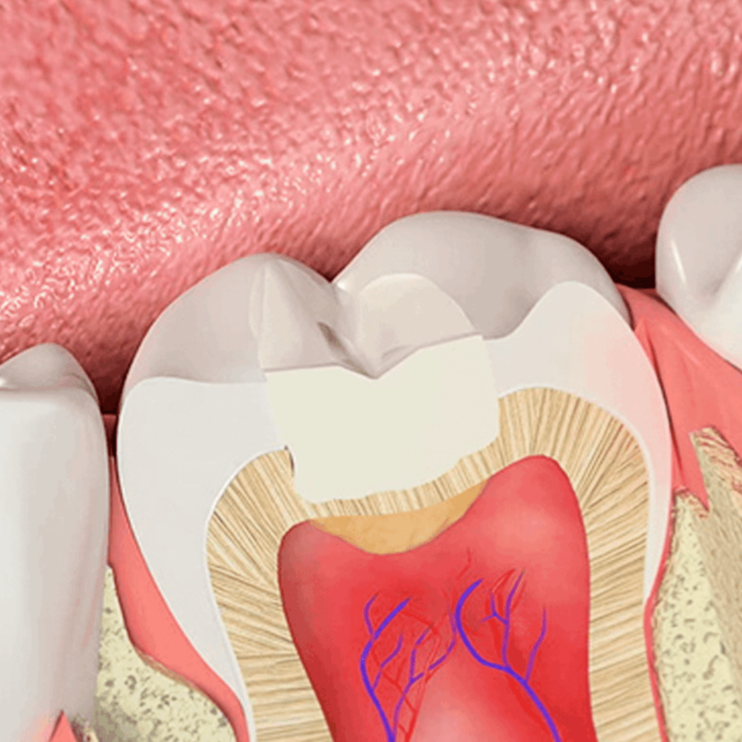

2. Κλινική εξέταση: Ο οδοντίατρος εξετάζει τα δόντια, τα γένεθλια, τη γλώσσα, τα χείλη και τα άλλα μέρη του στόματος για τυχόν προβλήματα όπως τερηδόντωση, καριές, περιοδοντική νόσο, κακοστομία και άλλα.

Ακτινογραφίες: Οι ακτινογραφίες, όπως οι πανοραμικές ακτινογραφίες και οι ακτινογραφίες με ροϊάντ, μπορούν να βοηθήσουν στη διάγνωση προβλημάτων που δεν είναι ορατά με το μάτι.

Διάγνωση και συστάσεις: Με βάση τις ευρήματα της εξέτασης, ο οδοντίατρος καθορίζει τη διάγνωση και προτείνει τον κατάλληλο σχεδιασμό θεραπείας.